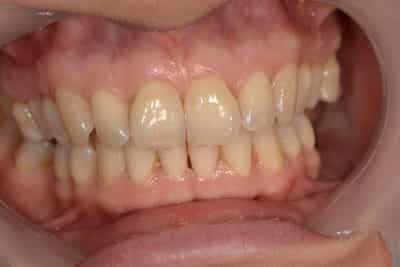

L’éclaircissement dentaire est une technique consistant à rendre aux dents une couleur plus harmonieuse, plus en adéquation avec l’image que le patient veut donner de lui. Le blanc des yeux est une référence. A l’échelle du visage, la blancheur de la sclérotique de l’oeil (blanc des yeux) fait ressortir la couleur jaune des dents. Pour une meilleure harmonie, il faut aligner ces deux couleurs. Si les dents sont moins lumineuses, l’éclaircissement va améliorer l’apparence. Après éclaircissement, cette différence s’atténuera et donnera une harmonie du visage.

Souvent, à partir d’un certain âge, les dents changent de couleurs. Ces changements peuvent être dûs à des colorations extrinsèques. Dans ces cas, un simple nettoyage-polissage peut suffire à y remédier.

Dans d’autres cas, il s’agit d’une usure de l’émail. L’émail est responsable de la luminosité de la dent, et son usure a tendance à révéler la couleur de la dentine sous-jacente. Elle peut être marron, jaune, grise, orange… L’éclaircissement agit sur les colorations intrinsèques et extrinsèques, en surface et en profondeur.